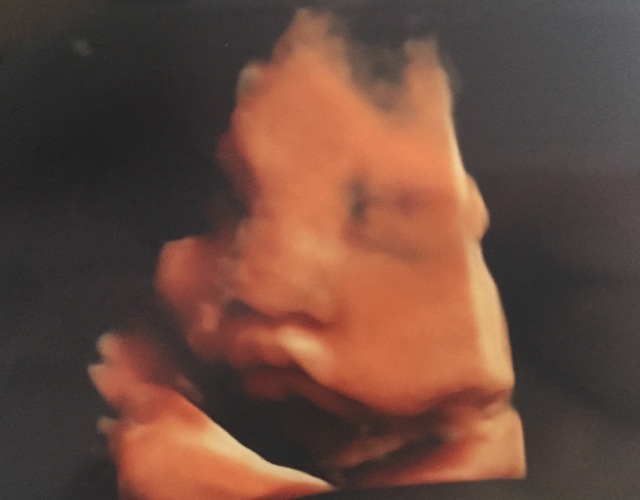

37週0日(37w0d・男の子)|ekna008 さん(27歳)

エコー写真撮影時のエピソード:

毎回3D.4Dで見るのを楽しみにしていたのですが、なかなか顔を見せてくれず妊娠中に4Dができたのは2回だけでした^_^!

最後は37週の時だったのですが、産まれてきてからの顔と比べて見るとそっくりでした!